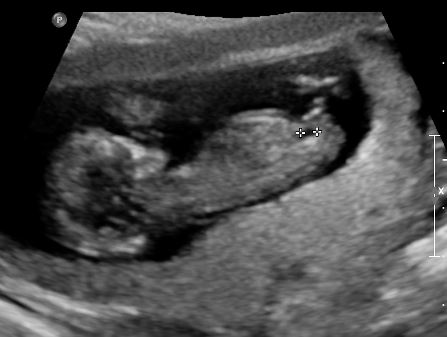

Pls guess girl or boy based on Nubs theory or skull theory?

12 weeks scan.

Heart rate 167

Boy!!!

Boy!

Looks very boy.

All boy!

100% boy